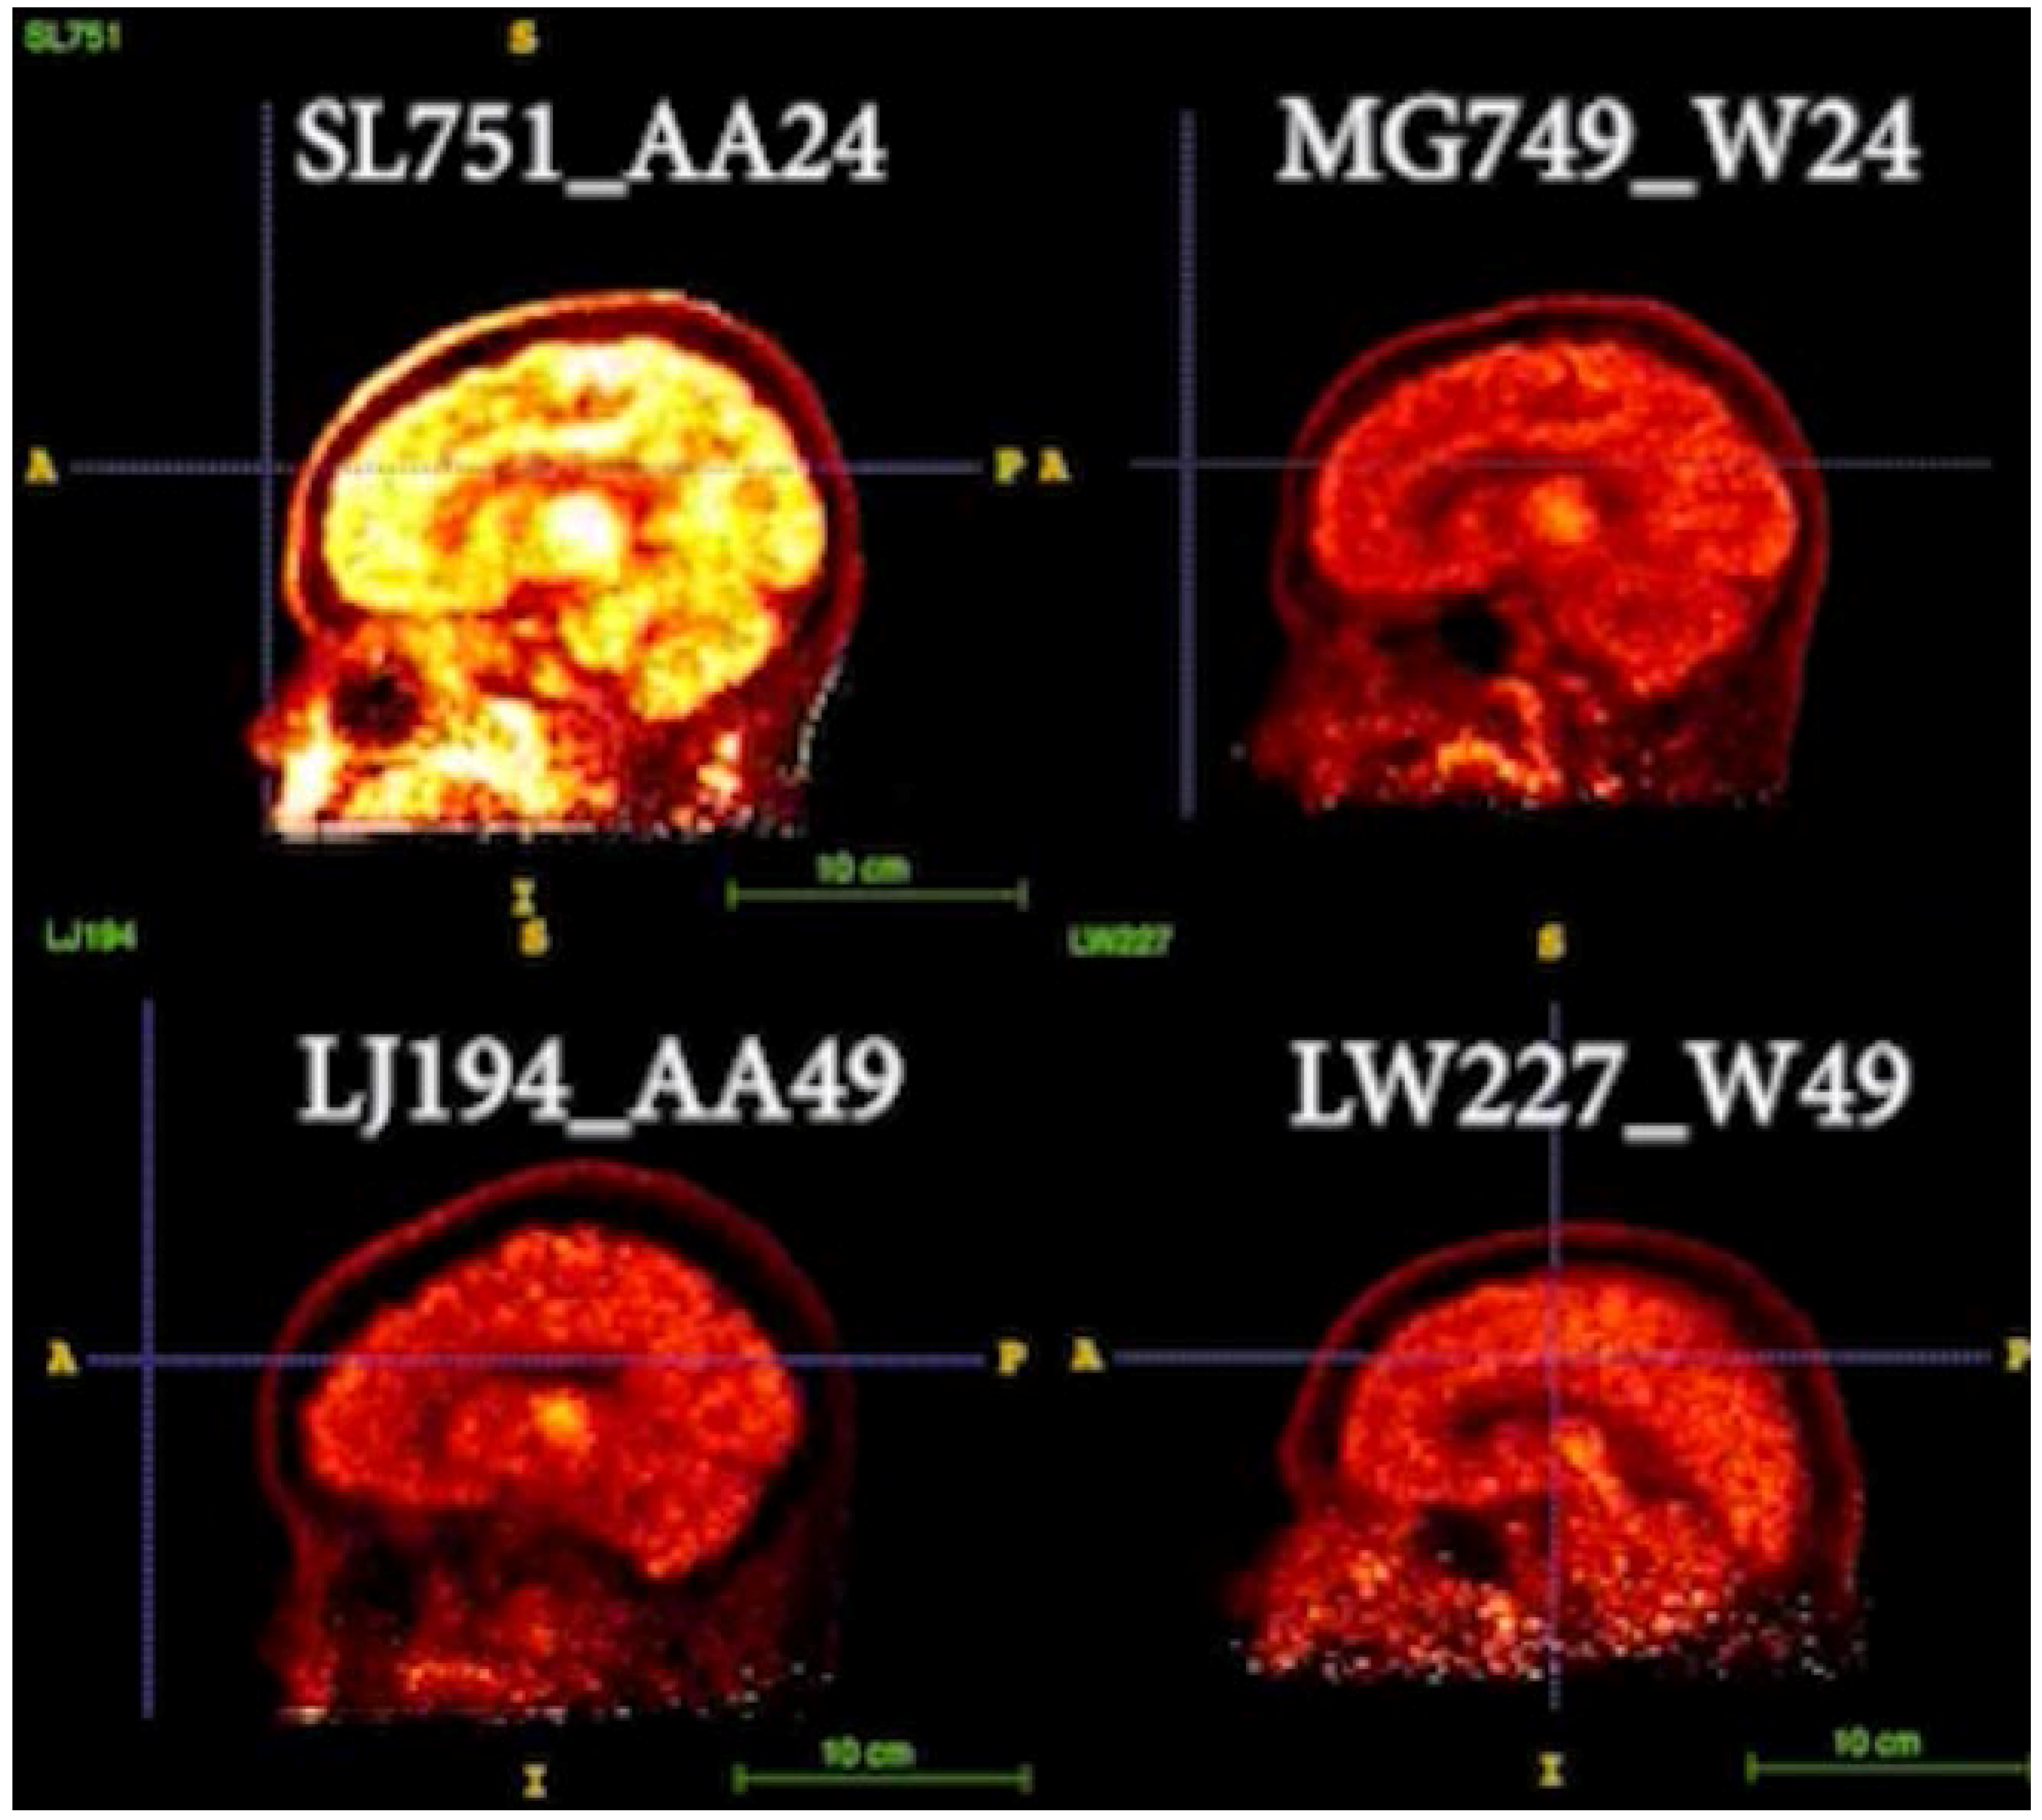

3.3. Representative Images